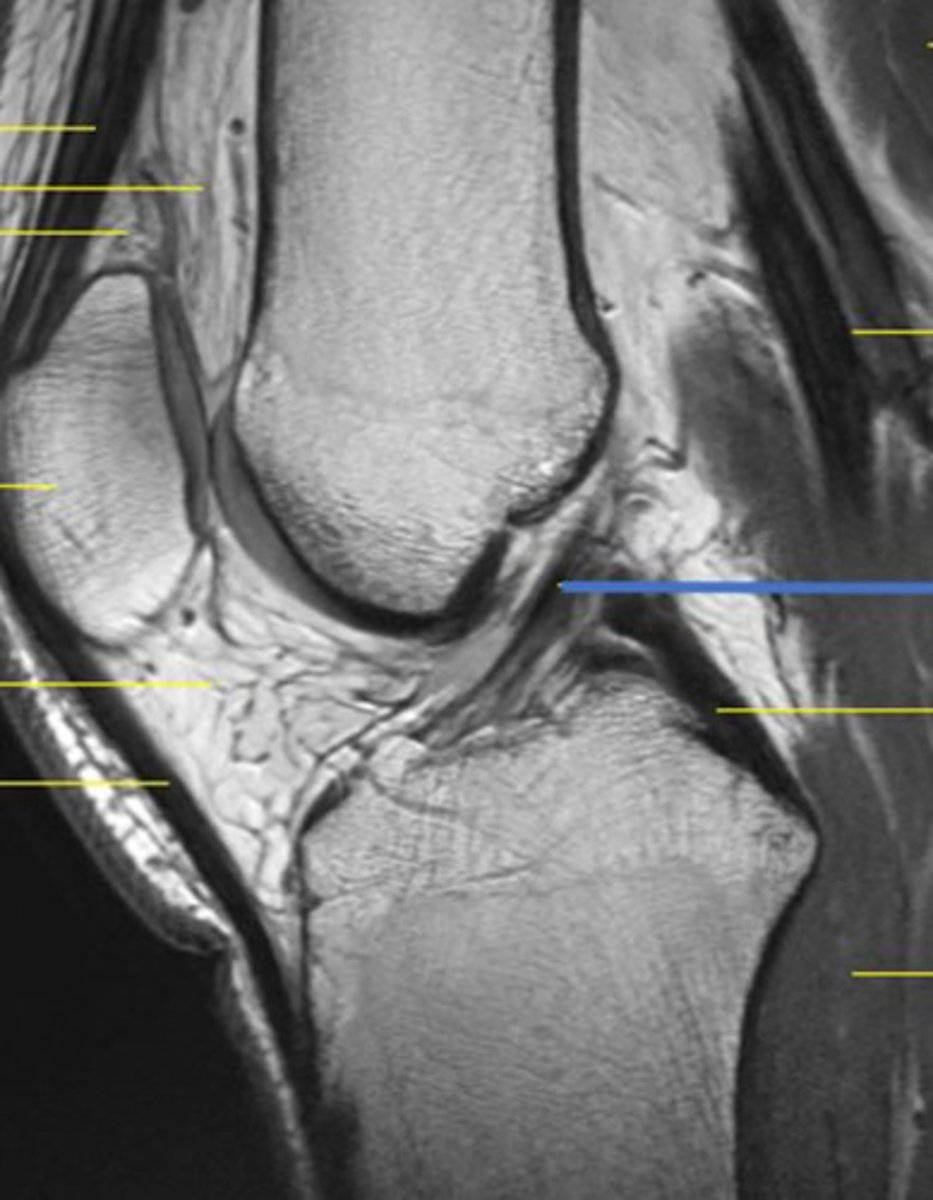

what structure is indicated by the orange arrow?

anterior cruciate ligament

3 multiple choice options

what grade would you classify the ligamentous tear in this MRI?

full-thickness

1 multiple choice option

identify the view of this magnetic resonance image (MRI)

sagittal view

2 multiple choice options

lateral meniscus, posterior horn

identify the view of this MRI

coronal view

what structure of the knee is highlighted by the blue line?

ACL